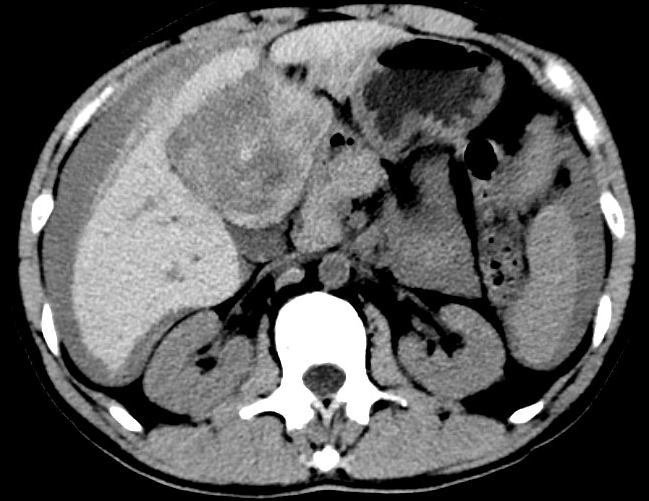

放下電話(huà)的白葦急赴消內(nèi)三搶救室會(huì)診,經(jīng)仔細(xì)查體、對(duì)患者腹部CT進(jìn)行詳細(xì)閱片、綜合評(píng)估患者后,考慮患者是肝占位破裂出血。患者病情十分緊急、一刻也不容耽誤,需立刻急診行肝動(dòng)脈造影 栓塞術(shù)進(jìn)行止血治療,在與患者家屬溝通后,立即通知消化介入室準(zhǔn)備急診手術(shù)。

入手術(shù)室時(shí),患者神志迷糊,口唇干燥、重度貧血貌,心電監(jiān)護(hù)提示:心率140-160次/分,血壓70/43mmHg,這是失血性休克的表現(xiàn)!白葦快速建立靜脈通道緊急給予輸血,升壓,止血等液,立即給予肝動(dòng)脈造影,術(shù)中發(fā)現(xiàn)肝左葉疑似腫瘤病灶、病灶周?chē)芊种в性煊皠┩庖纾紤]血管破裂出血,迅速給予栓塞微球進(jìn)行肝動(dòng)脈栓塞。整個(gè)手術(shù)過(guò)程不足20分鐘,術(shù)后即刻患者心率降至100-110次/分、血壓升至90/60mmHg。

術(shù)后給予積極抗炎,止血,保肝、利尿等對(duì)癥治療,復(fù)查血常規(guī)提示活動(dòng)性出血停止后,在超聲引導(dǎo)下行腹腔穿刺引流術(shù),術(shù)后3天共引流出血性腹水約4000ml。患者經(jīng)復(fù)查各項(xiàng)指標(biāo)均趨于正常,復(fù)查CT提示腹腔積血已基本吸收,患者康復(fù)出院。